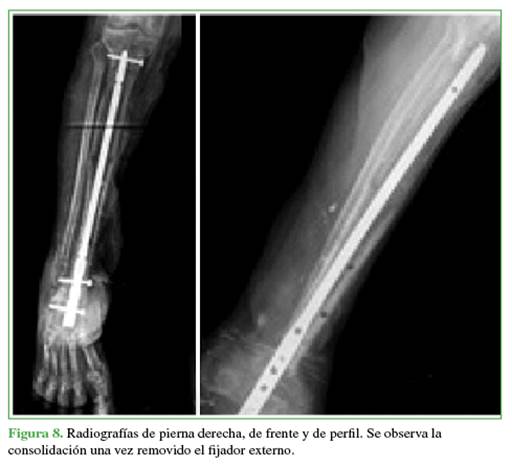

Una vez completado el transporte óseo, los pacientes pasan a la etapa de compresión del sitio de acoplamiento (Figuras 7 y 8). Esto se llevó a cabo mediante el sistema de transporte o la compresión con una placa de compresión dinámica sin invadir el foco (Figura 9).